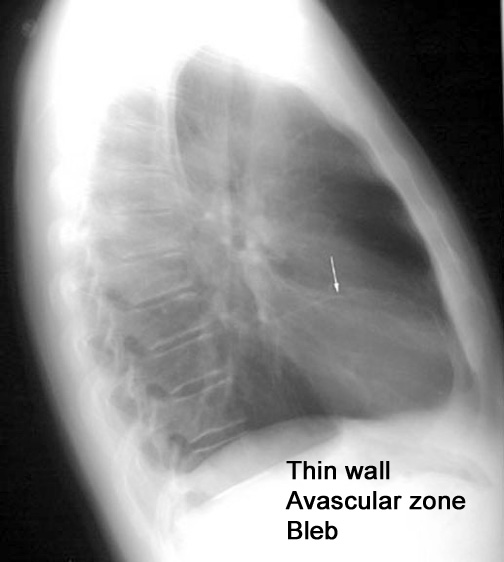

Case 1 Labeled Image What are the conditions where you get thin walled cavities?